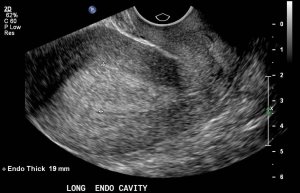

Лікар вже при первинному візуальному огляді може припустити, що у жінки гіперплазія ендометрію. Для остаточної постановки діагнозу потрібно пройти ультразвукове дослідження.

Проводиться УЗД органів малого тазу. Воно дозволяє отримати наступні дані:

- локалізація потовщень

- товщина наросшего ендометрію в міліметрах

- наявність поліпів

Якщо ендометрій незмінний, то його товщина складе приблизно 9,8 мм, якщо є гіперплазія, товщина ендометрія підвищується до 15,4 мм, при железистом раку товщина перевищує 20 мм.

Точність УЗД становить 60%, точність гістероскопії 95%.